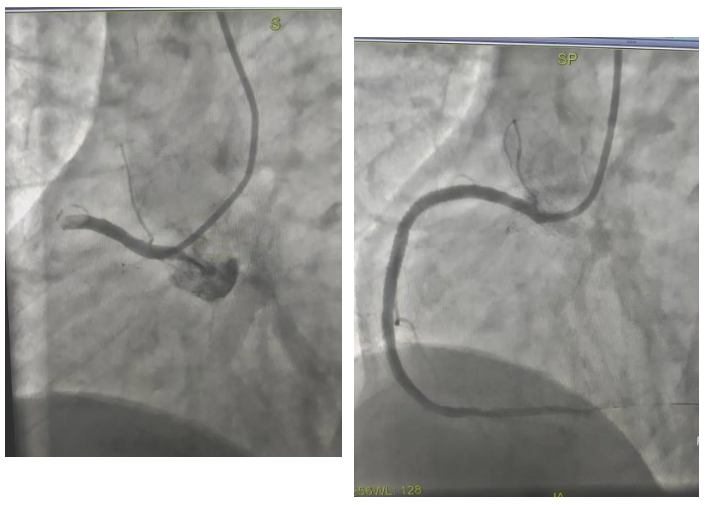

2月19日,祝阳镇卫生院接诊一名患者,仅表现为胸闷1小时,前一日夜间心电图还显示正常。基层医生敏锐捕捉到病情变化,将复查心电图上传至群内。王秀主任第一时间研判为急性下壁心肌梗死,指导立即启动急救流程。患者入院后造影显示右冠开口完全闭塞,介入团队迅速实施手术,成功开通血管,将患者从死亡线上拉了回来。

春节假期期间,胸痛中心先后完成8台急诊介入手术。其中,一名73岁老年女性因呕吐、上腹痛由祝阳卫生院转诊,看似胃肠症状的背后,实则是前降支完全闭塞。面对患者肱动脉严重狭窄、锁骨下动脉迂曲的复杂情况,介入团队迎难而上,更换手术途径,成功为患者植入支架,打通生命通道。